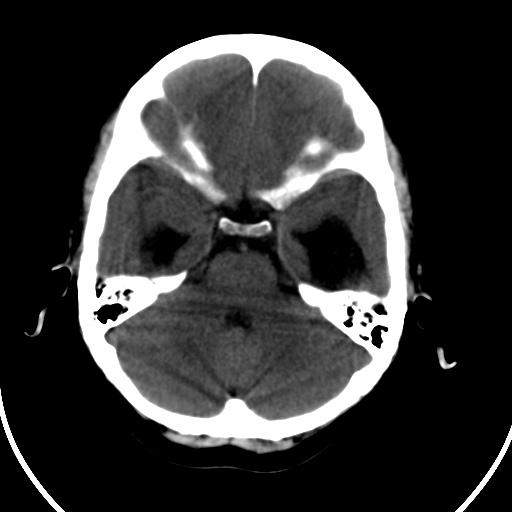

男,11岁

重度脑积水,但第四脑室扩大不明显,考虑导水管阻塞,建议mr。

右额叶单发近圆形低密度影,周边光滑,与侧脑室相通,考虑为孔洞脑并阻塞性脑积水。

右额叶内见一边界清楚,脑脊液密度的囊腔,无灰质内衬,并与脑室相通,四室以上脑室系统高度扩张。诊断:先天性脑穿通畸形伴梗阻性脑积水

脑穿通畸形并梗阻性脑积水.